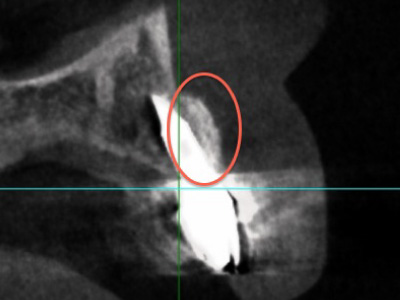

先述したように、非常に薄い骨の中にインプラントの埋入が求められることに加え、前歯のインプラント治療で審美的な仕上がりを実現するためには、インプラントの埋入位置が極めて重要です。わずか1 mmのズレや角度が5度違うだけで、最終的な見た目に大きな影響を与えるためです。ねじれた位置に埋入されと歪な被せ物しか作れなくなります。

また、特に下顎の前歯は神経が近いため、インプラント手術の際に神経が損傷するリスクがある点も難易度を高める要因の一つです。そのため、前歯のインプラント治療では、シミュレーションソフトを用いた精度の高い埋入計画が不可欠です。シミュレーションソフトにより、正確な位置にインプラントを埋入するための情報が得られます。

シミュレーションソフトを用いて正しいポジションにインプラントを埋入。

インプラントは骨の中に入るようにできるだけ細いものを使用していますが、それでも骨造成は必要です。

インプラント周りに骨造成も実施しました。